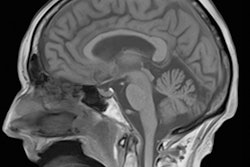

Researchers from the U.K. (University College London) and Germany (German Center for Neurodegenerative Diseases [DZNE], Magdeburg; Max Planck Institute, Leipzig; and Ruhr University, Bochum) have used ultrahigh-field functional MRI (fMRI) to produce a precise topographic map of the representation of touch in area 3b of the somatosensory cortex -- a region thought to only respond to mechanical stimulation.

The auditory, somatosensory (tactile), and visual cortices have detailed spatial organization. For instance, subregions of the somatosensory cortex that respond to finger touch lie next to each other in a neat pattern. Here, the researchers employed ultrahigh-resolution (7-tesla) fMRI to investigate whether area 3b responds when a subject observes someone else's fingers being touched, and if so, whether there is specific finger organization.